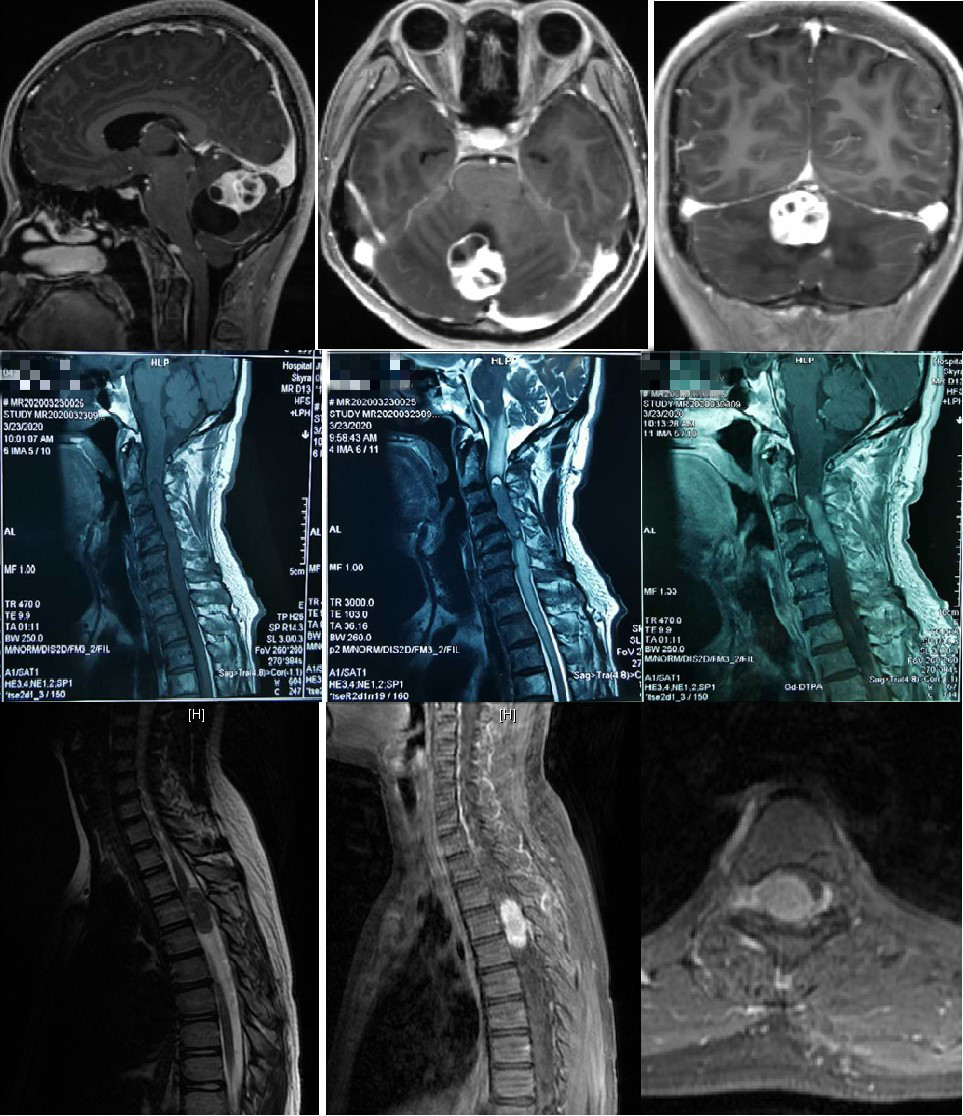

图6 近期我院神经外科手术治疗的部分患者核磁影像

据王贵怀主任介绍,张先生罹患的是一种脊髓髓内肿瘤,很多病人长时间都没有明确症状,有些人会有“颈椎病”类似的表现。从患者目前的影像检查和病史来判读,考虑是室管膜瘤,它是脊髓常见的髓内肿瘤,这种病药物无法治愈,只能通过手术治疗,如果能够做到全切,术中对正常神经充分保护的话,病人将开启下一段正常的人生。但是肿瘤位置特殊,长在延髓到颈3椎体水平的脊髓内,手术需要切开脊髓进行,稍有不慎就会导致病人瘫痪,甚至呼吸心跳骤停,手术风险和难度极大。

图4 患者术后复查磁共振提示肿瘤全切